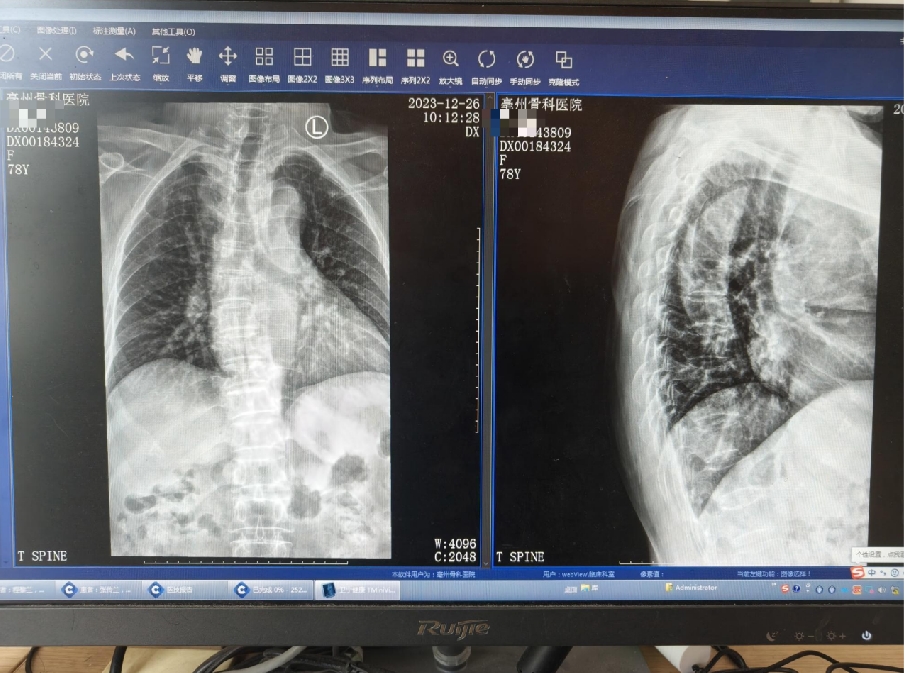

做了个叫做MRI的高级检查,结果显示她的胸椎有些老化变化,第9节胸椎骨头被压扁了,里面还有些水肿。